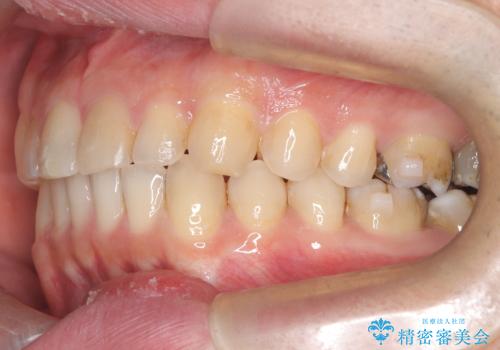

- 前歯の隙間と歯のデコボコを主訴にご来院された患者様です。

加えて、上下の奥歯が全く咬み合わないシザーズバイトの状態も認められました。

矯正検査の結果、非抜歯でインビザラインによる治療が可能と判断し、治療を行いました。

歯の隙間とデコボコ、シザーズバイトも改善され、咬み合わせや見た目が整い、患者様にも大変ご満足いただけました。